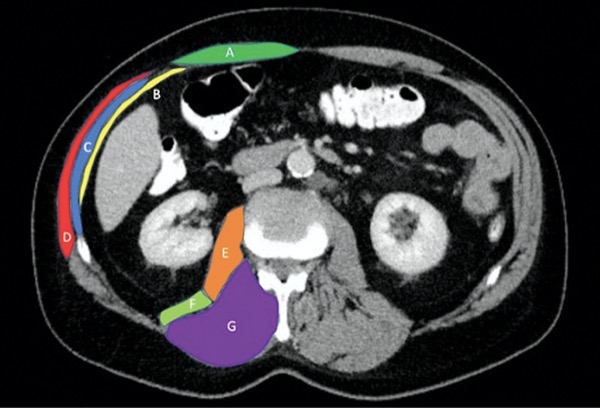

Regarding the defect aspect of the report, the precise location of the defect in relation to various reference points is critical. The authors suggested the umbilical stalk, xiphoid and pubic symphysis be used as a reference for midline hernias; costal margin, iliac crest, semilunaris line and the midline should be used as a reference for lateral hernias. The size and number of defects and their locations must also be included.6 A description of the hernia contents must focus on whether viscera, such as small bowel, or fat is present within the hernia sac. Additional information regarding whether the small bowel is incarcerated or strangulated can change the urgency or emergency status of a case. The content section of the report should also include information regarding the volume of the hernia sac in relation to the volume of the abdominal cavity to determine the extent, if any, of loss of domain. The muscular section should focus on whether or not the patient has diastasis recti, the width of the rectus muscles, whether there is muscular atrophy or rupture present, and whether an intraparietal hernia exists. Lastly, the previous events section should focus on any evidence of previous surgical events, such as evidence suggesting a component separation or the presence of mesh.6